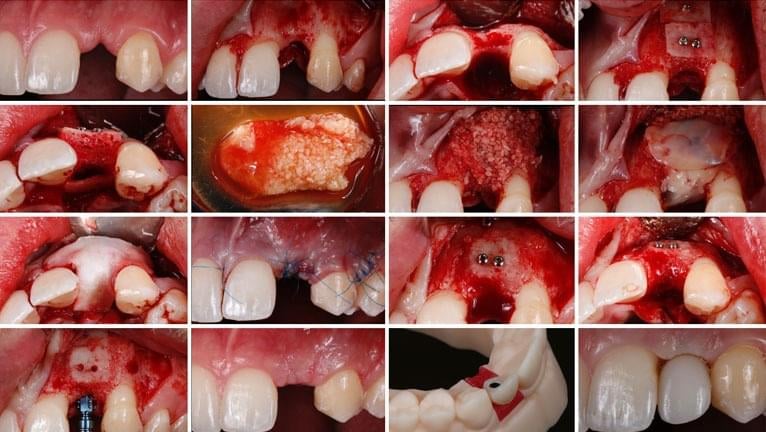

GBR CASE STUDIES- PREDICTABLE SYSTEMS AND TECHNIQUES

Placing dental implants? Over 40% of all dental implants require some form of bone grafting. Join Dr. Naheed Mohamed and Dr. Stephen Phelan for a free webinar training that will teach you how to be confident and successful with your bone grafting procedures.

Using actual cases from Dr. Mohamed’s specialty practice this presentation will focus on a systematic approach to treatment planning and executing a successful GBR procedure.